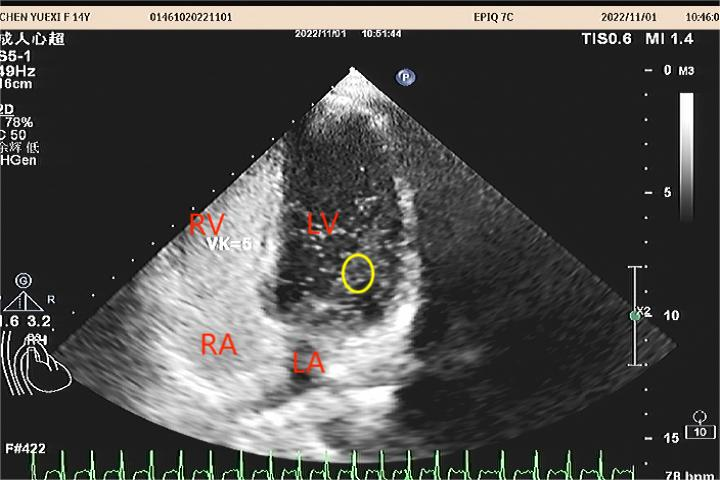

图2:在某些情况下如咳嗽、大笑、打喷嚏、“Valsalva动作”时,出现一过性的右房压力升高、超过左房压,导致左侧薄弱的原发隔被推开,出现右向左分流,如上图,黄色圈内为由右心分流至左心的微气泡。